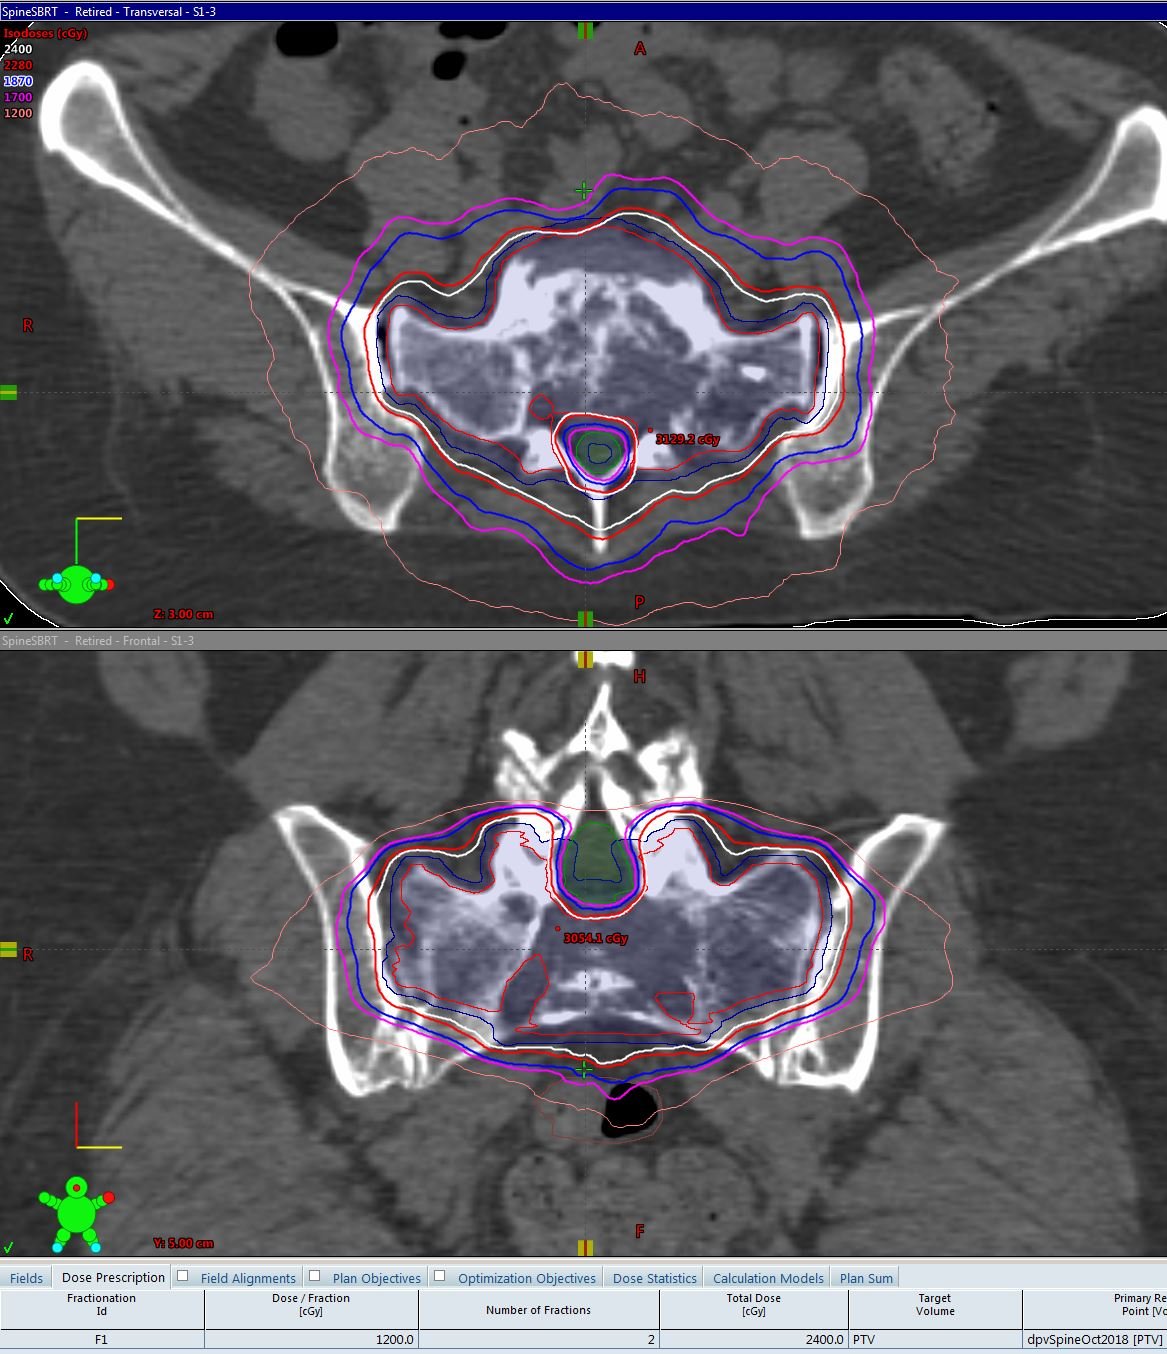

Stereotactic Body Radiation Therapy (SBRT) and Stereotactic Ablative Radiotherapy (SABR) require extreme precision. We provide meticulous planning for these high-dose-per-fraction treatments, ensuring steep dose gradients and maximal organ protection.